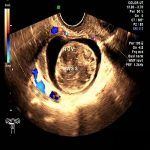

卵巢囊肿常用的检查 2020/04/09 分类:卵巢囊肿 2048 0卵巢囊肿常做的检查有全景四维彩超、电化学发光激素六项、CA125辅助诊断,3D腹腔镜、病理最后确诊。 标签:卵巢囊肿检查 上一篇: 卵巢囊肿感染因素 下一篇: 卵巢囊肿盆腔全景超声